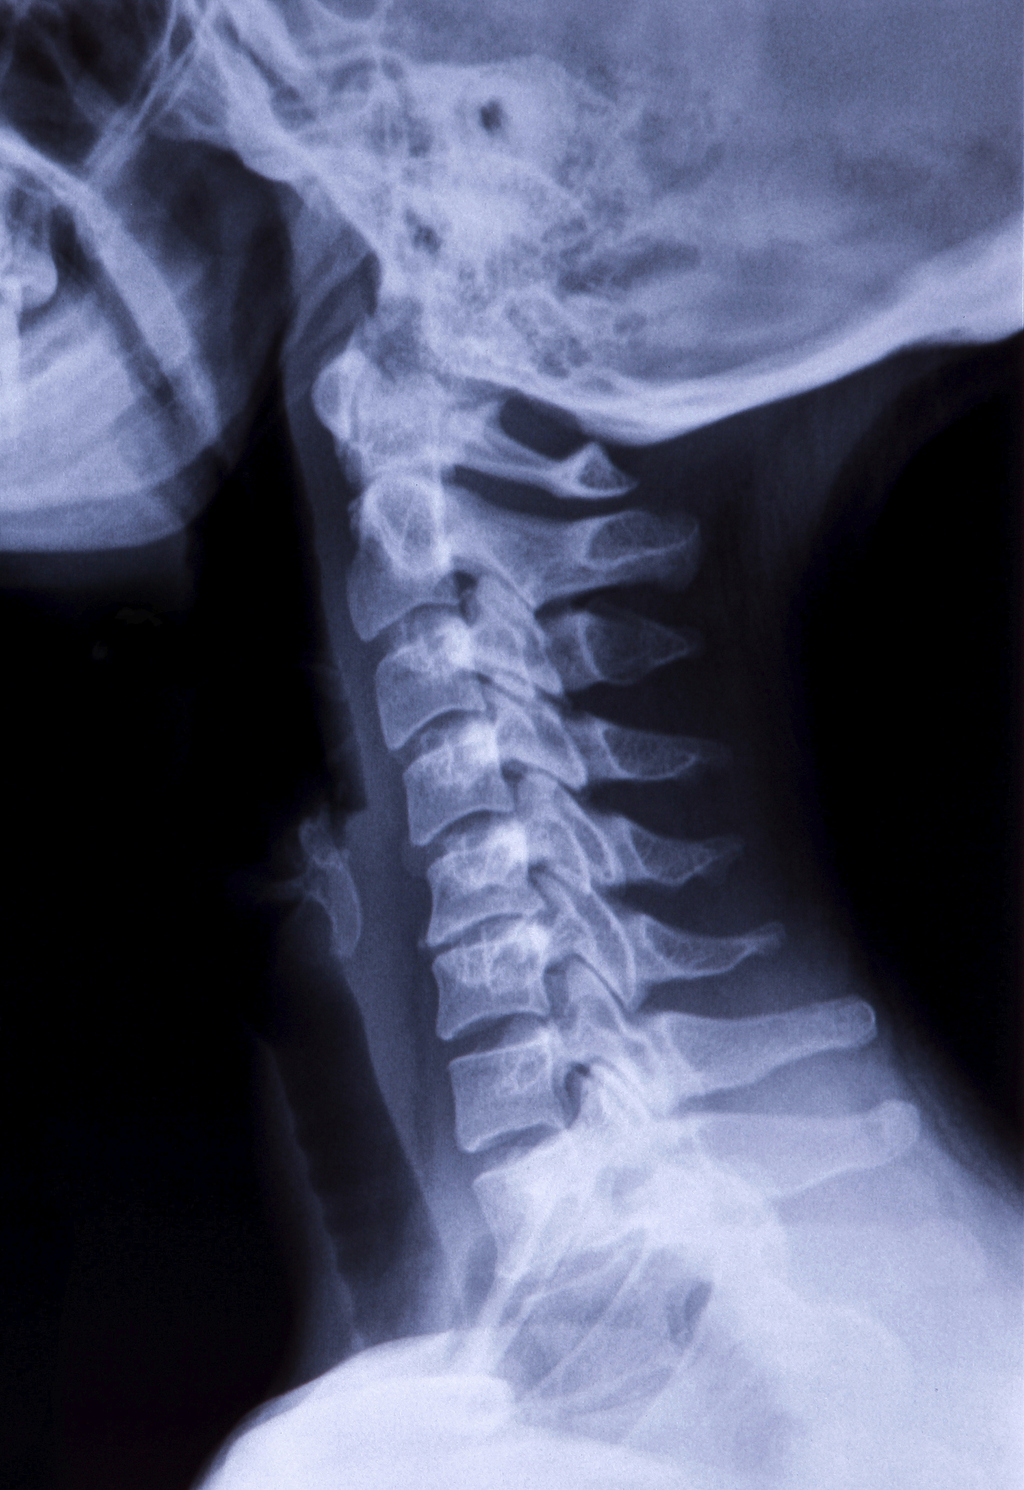

Joint Pain in the Neck The Buxton Osteopathy Clinic

From www.buxtonosteopathy.co.uk

Joint Pain in the Neck The Buxton Osteopathy Clinic Bone In Neck That Breaks When Strangled Observation of hyoid fracture in skeletonized remains offers potentially valuable information on the history of the skeleton or evidence of foul. Strangulation injuries are a heterogeneous set of traumatic pathology that occurs as a result of mechanical force applied externally to the neck and. We report a comprehensive review of a case of hyoid bone fracture associated with head and. Bone In Neck That Breaks When Strangled.